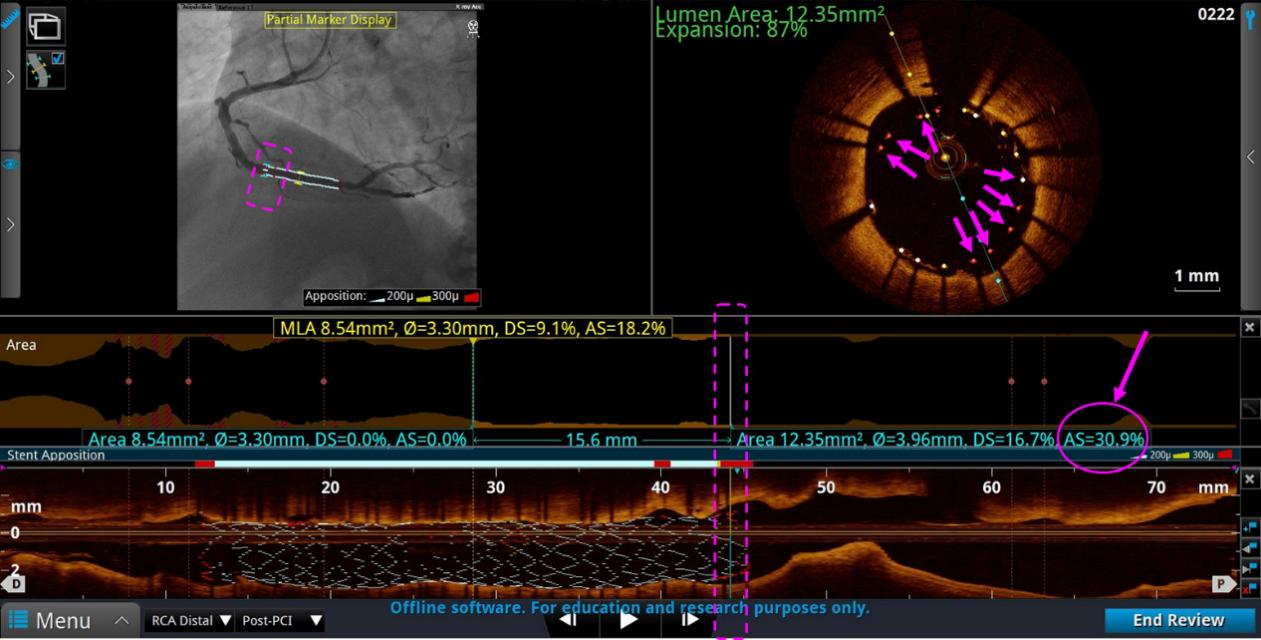

2、ACR造影融合——评估支架扩张情况

远端评估:支架远端边缘如果AS(面积狭窄率)≥20%,则需要进一步扩张处理。

近端评估:支架近端边缘如果AS(面积狭窄率)≥20%,则需要进一步扩张处理。